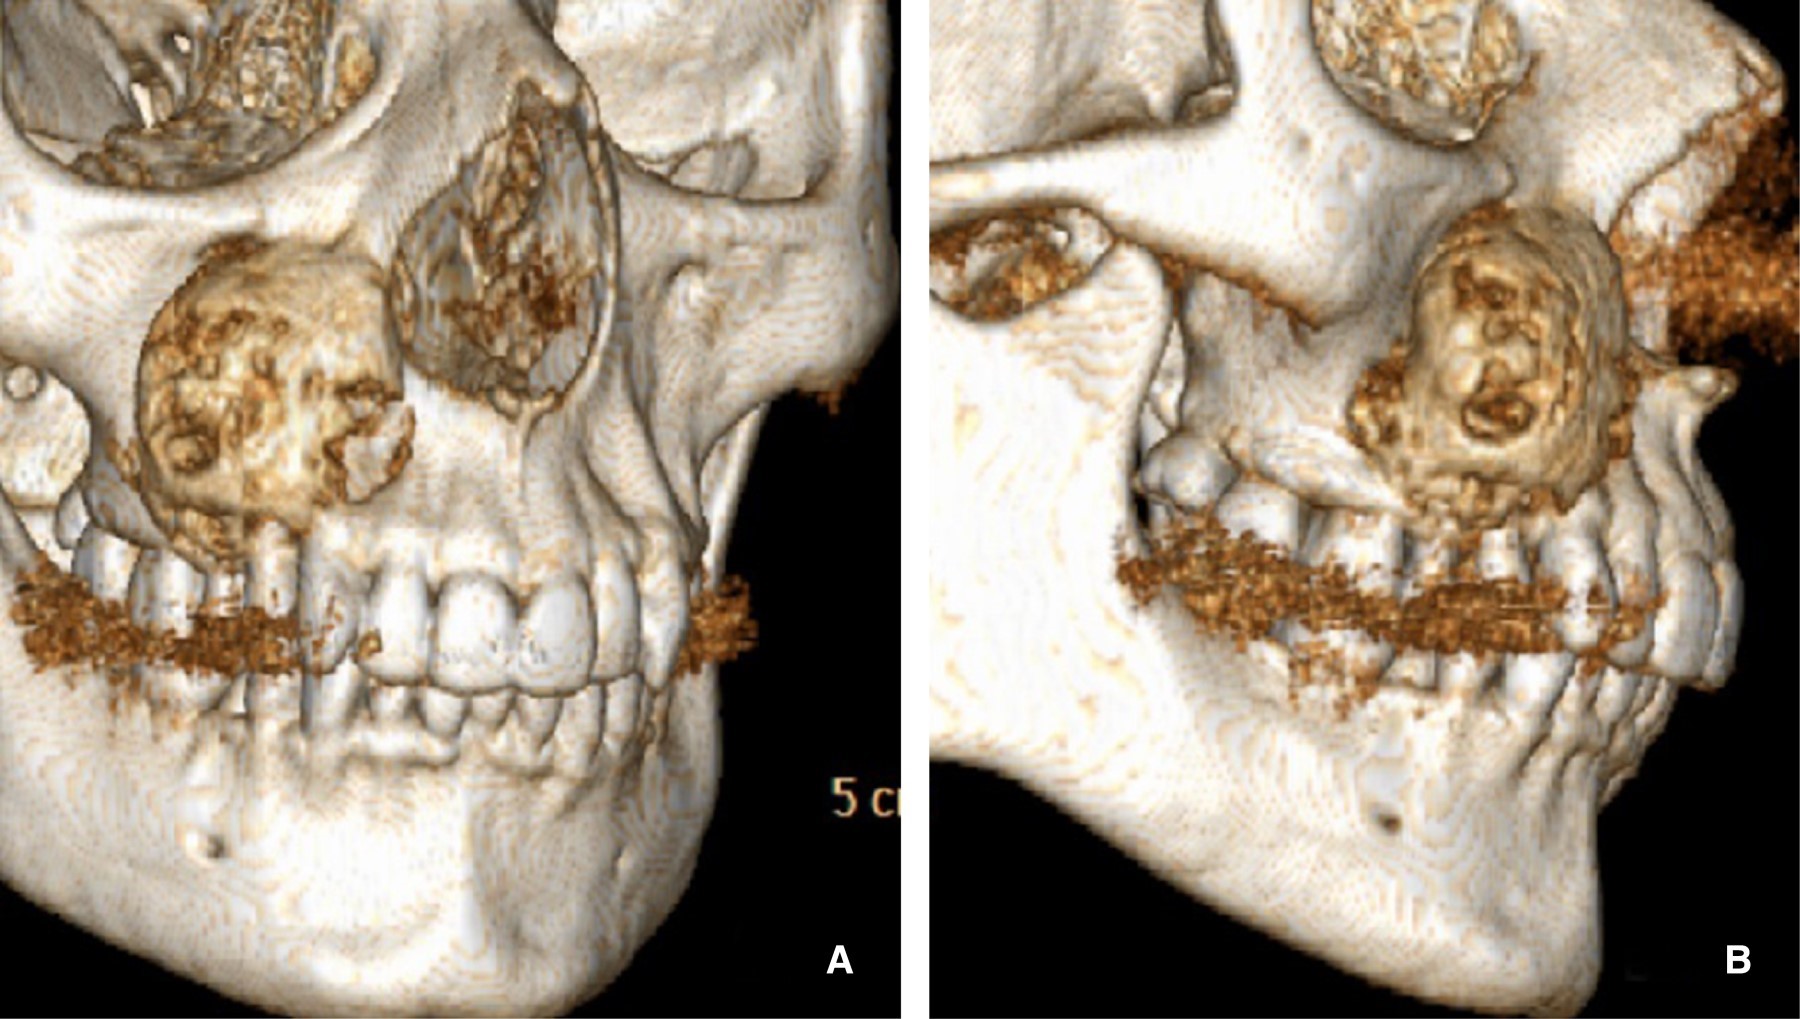

Se inicia el protocolo de infiltración intralesional, tomando como base el protocolo descrito por Jacoway, se infiltran 3.5 mL de acetónido de triamcinolona con 3.5 mL de lidocaína a 2% con epinefrina al 1:100,000 una vez por semana, hasta completar seis aplicaciones, una vez concluidas las mismas, la tumoración disminuyó de manera discreta (Figura 2), por lo que se realiza bajo anestesia general balanceada, la enucleación y curetaje de la lesión, se retira de manera completa el espécimen; mismo que se deposita en formalina al 10% (Figura 3).

Figura 2